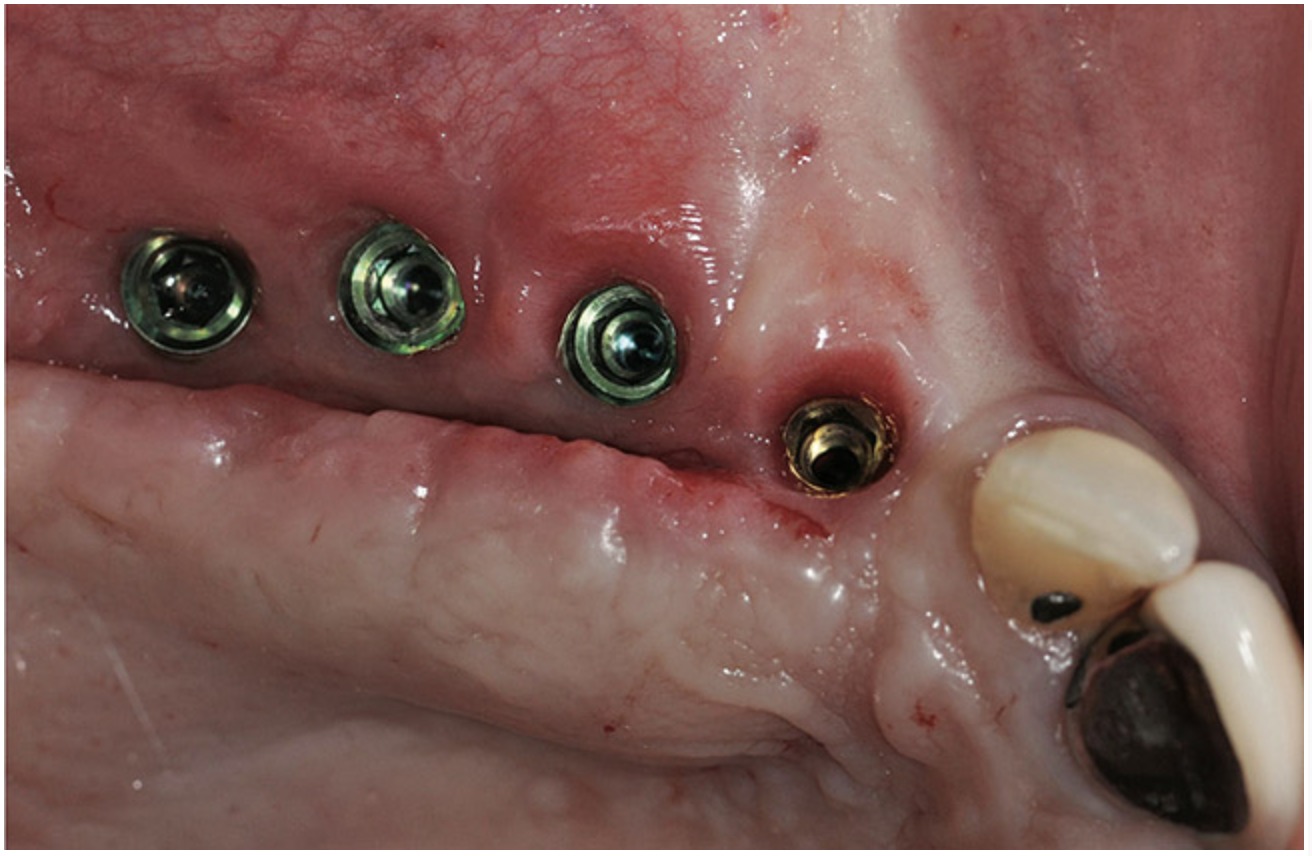

A 62-year-old woman was referred for fixed tooth replacement of the missing maxillary left cuspid, bicuspids, and first molar (Figure 11). Clinical and CBCT evaluation revealed an almost fully pneumatized maxillary left sinus along with alveolar width deficiency. The treatment plan called for a four-unit, implant-supported splinted fixed bridge. A left sinus augmentation along with a ridge split and interpositional bone graft consisting of rhBMP-2/ACS (INFUSE Bone Graft) and mineralized allograft (MinerOss) covered by a dense porous polyethylene mesh (Medpor®, Stryker, www.stryker.com) were done simultaneously (Figure 12, Figure 13 and Figure 14). Six months later, a follow-up CBCT revealed a well-incorporated graft with adequate bone volume and density for implant placement (Figure 15 and Figure 16). Final bridge fabrication followed 3 months later (Figure 17 and Figure 18).

Figure 11  Edentulous left posterior maxilla with alveolar ridge deficiency.

Figure 11

Figure 17  Implant placement into augmented ridge at 7 months.

Figure 17

Figure 18  Three months after implant placement, but before soft-tissue vestibuloplasty.

Figure 18